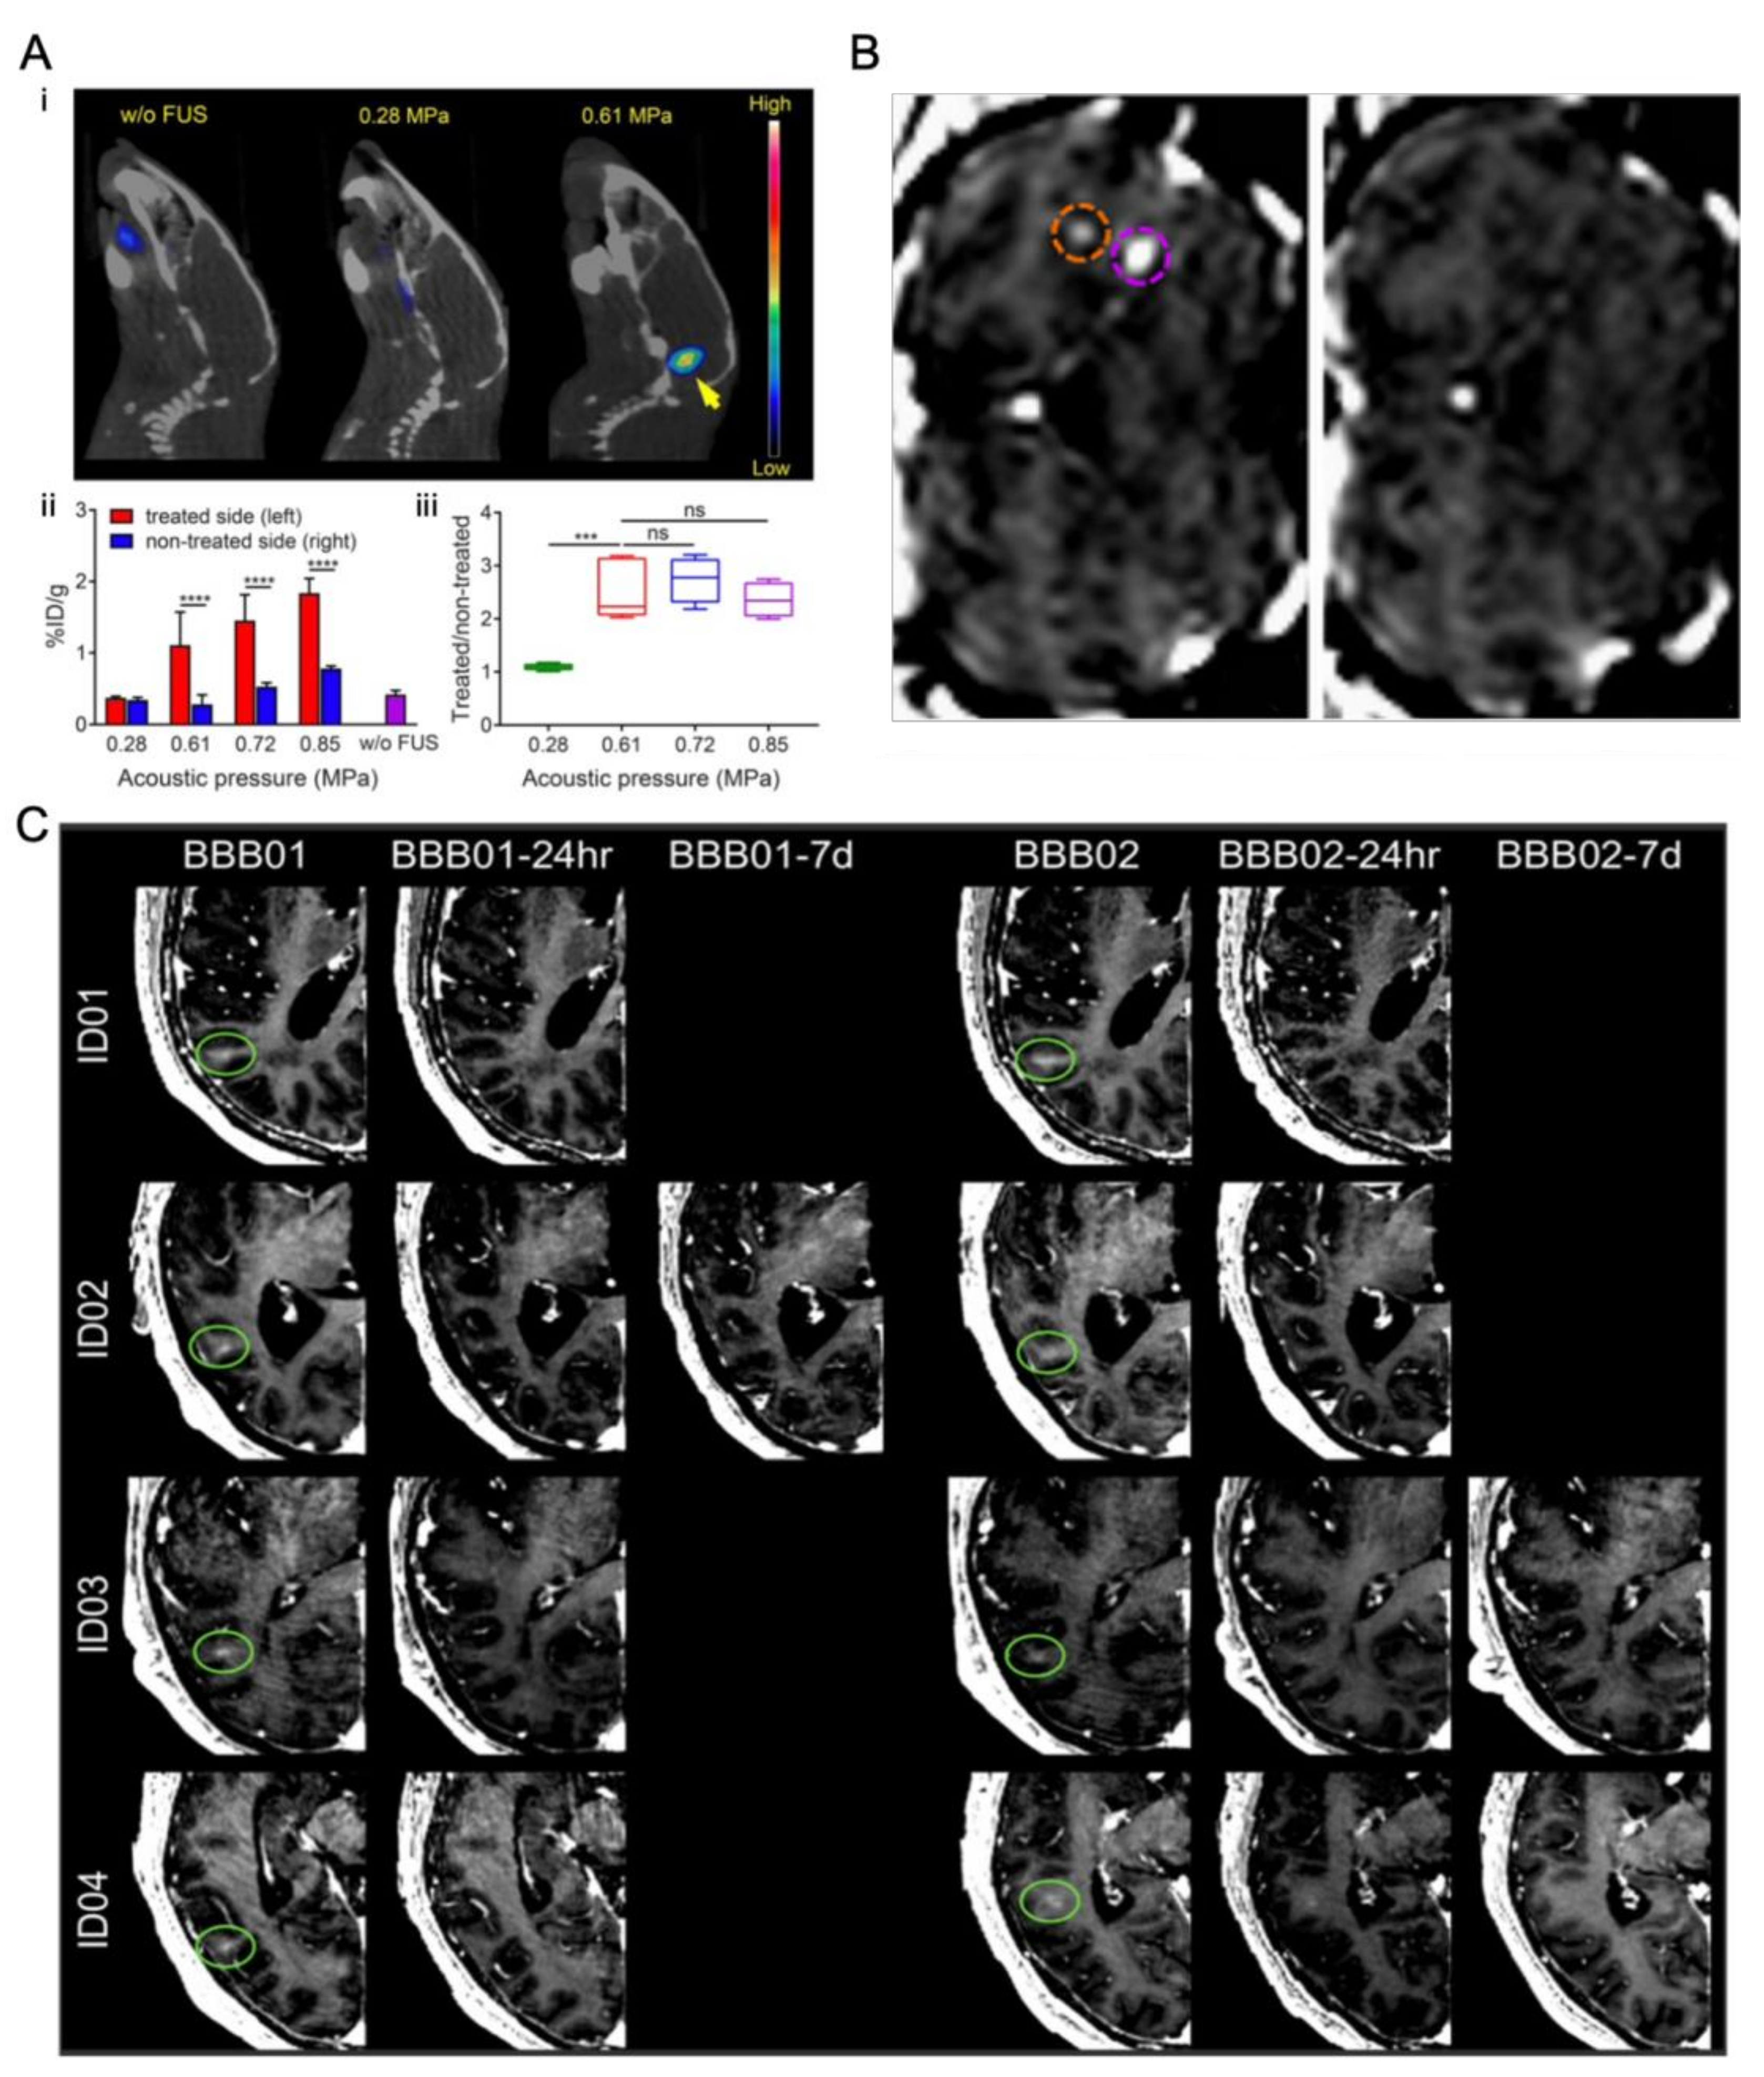

4.2.1. In Vivo Experiments

4.2.2. In Vitro Static System